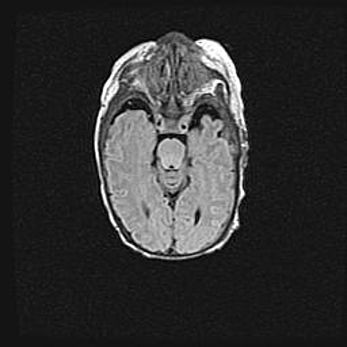

Открытая гидроцефалия.

Возраст: 9 месяцев 12 дней

Вес: 6800 г

Пол: мужской

Окружность головы: 41,5 см

Срок гестации: 28 недель

Гидроцефалия головного мозга у новорожденных имеет характерный признак: опережающий рост окружности головы приводит к визуально хорошо определяемой гидроцефальной форме сильно увеличенного в объёме черепа. Детские неврологи определяют следующие симптомы гидроцефалии у грудничков: выбухающий напряжённый родничок, частое запрокидывание головы, смещение глазных яблок к низу.